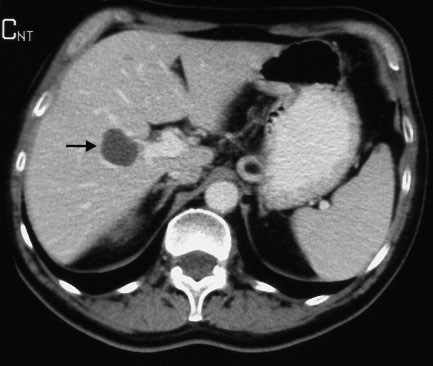

Even though Gemella morbillorum infection (GMI) is rare in humans, it may, nevertheless, cause endocarditis, meningitis, brain abscess, pleural empyema, nephritis, mediastinitis, and – occasionally – liver abscess. We are describing the case of a 64-year-old Caucasian male admitted with fever and abdominal pain. Laboratory parameters revealed inflammation signs, and instrumental examinations showed the presence of diverticula in the ascending colon. Abdominal ultrasound (US) and computer tomography (CT) showed two focal lesions in the right liver lobe. One had the characteristics of a simple cyst; the second was hypoechoic with a low density area, possibly containing necrotic material. US-guided needle biopsy was found negative for neoplastic cells, showing purulent infiltrate. Pus culture was found positive for GMI. Systemic antibiotic therapy, coupled with repeated US-guided needle aspiration, induced the resolution of the hepatic abscess. Few cases have been reported of hepatic abscess caused by GMI in immunocompetent non-cirrhotic subjects.Authors